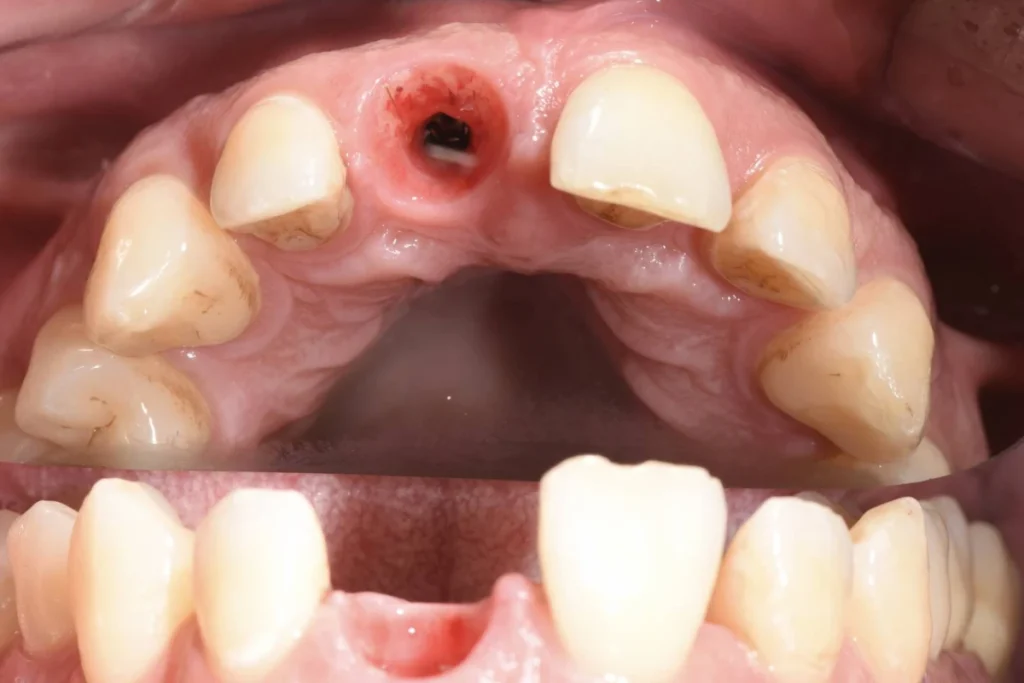

Cas clinique 1 – Remplacement d’une incisive centrale par un implant dentaire et une couronne tout céramique

Mr M., 33 ans, se présente à la consultation suite à un traumatisme survenu à la boxe. La facette dentaire réalisée il y a plusieurs années par un confrère a été perdue après un coup encaissé au visage.

Le patient souhaite remplacer sa prothèse pour pallier au préjudice esthétique en urgence. Malheureusement, la dent présente une carie qui ne permet plus de conserver cette dent. Une dent provisoire est réalisée au cabinet afin de gérer l’urgence esthétique évidente et de permettre au patient de réfléchir aux soins proposés « à tête reposée » 🙂

Après un traitement parodontal initial nous permettant de mettre l’environnement buccal dans les meilleures conditions pour l’intervention, nous décidons avec le patient de planifier la chirurgie. Un protocole d’extraction implantation et mise en esthétique immédiate est décidé afin d’éviter au patient le port d’une prothèse amovible.

Le patient repart du cabinet avec une couronne fixée à l’implant tout juste mis en place! En contre partie, le patient devra faire l’effort de ne pas solliciter sa dent lors des repas afin de laisser l’implant s’ostéo intégrer (se souder) à l’os.